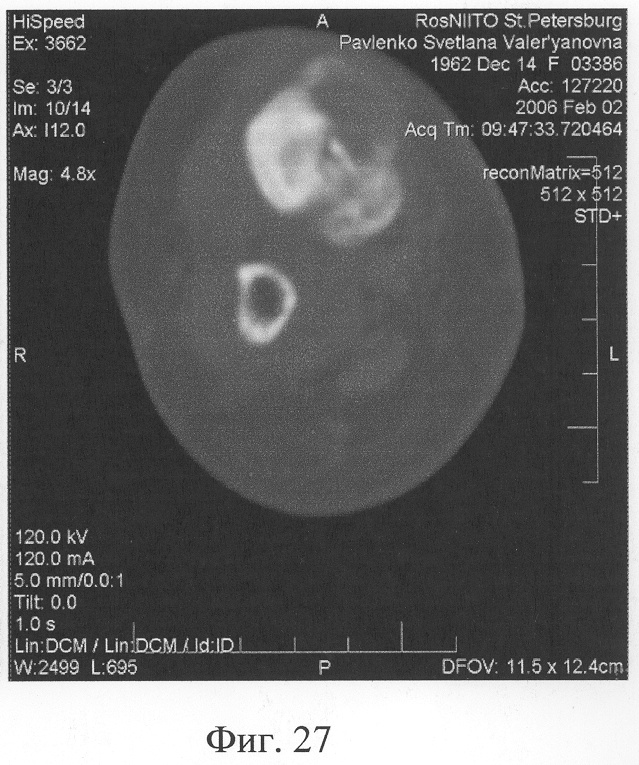

Аппарат внешней фиксации с левой голени демонтирован через 3 месяца после операции при клинико-рентгенологической картине сращения перелома. Аппарат внешней фиксации с правой голени демонтирован через 7 месяцев после операции при клинико-рентгенологической картине сращения перелома (фиг.20-25 – результат лечения). При рентгенологическом и томографическом контроле в трансплантатах отмечалось постепенное нарастание плотности костной ткани с формированием костной мозоли на всем протяжении между трансплантатом и костными фрагментами (фиг.26-29 – динамика данных компьютерной томографии правой голени: отмечается нарастание плотности костной ткани в области трансплантатов и формирование регенерата между смещенным трансплантатом и костными фрагментами; фиг.30-33 – динамика данных компьютерной томографии левой голени: отмечается нарастание плотности костной ткани в области трансплантатов и формирование регенерата между трансплантатом и костными фрагментами).